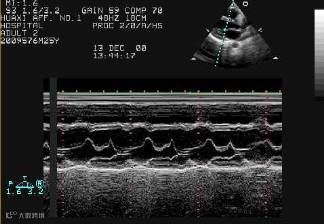

2、M型超声诊断仪(motion)

M型超声诊断仪是在A型超声诊断仪基础上发展来的一种最基本的超声诊断设备。其显像管上的亮度表示回波幅度,由A型回波幅度加到显像管Z轴亮度调制极上所控制;其纵轴表示超声脉冲的传播时间,即探测深度;显像管水平偏转板加一慢时间扫描电压。这样在做人体探查时,就构成一幅各回波目标的活动曲线图。

M型超声诊断仪在检查心脏时具有一系列优点,如对心血管各个部分大小、厚度、瓣膜运动的测量,以及研究心脏的各部分运动与心电图、心音图及脉搏之间的关系等,所以也称超声心动仪。此外它还可以研究其他各运动界面的情况,并通过与慢时间扫描同步移动探头,做一些简单的人体断层图。